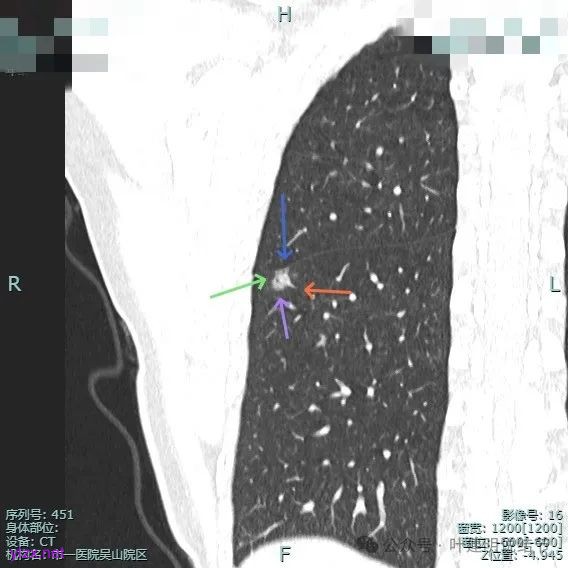

此层见囊壁有较明显实性成分,血管进入明显。叶间裂侧平直。

混合密度,收缩力不明显,血管进入明显。

囊壁混合密度,整体轮廓清。

表面不平,血管进入,囊壁厚薄不均,紧贴叶间裂。

囊壁里面也有小空泡征。

混合密度但还是太致密,内壁毛糙不平。

病灶轮廓清楚,囊壁厚薄不均,贴着叶间裂与胸膜。